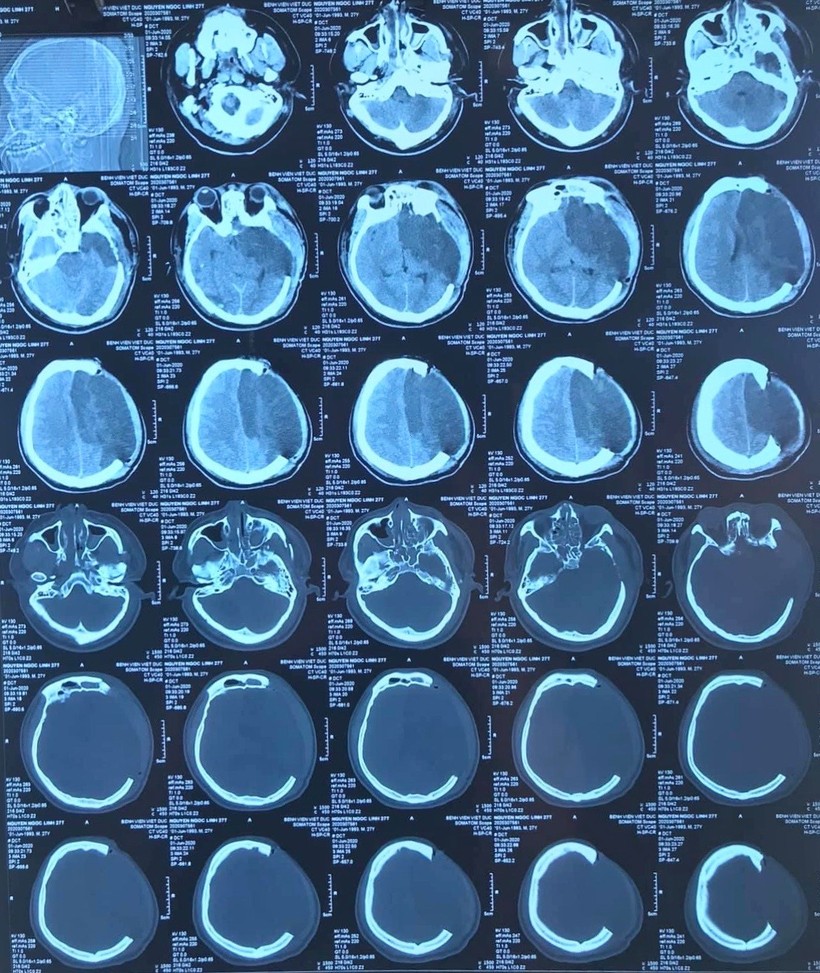

Anh N.N.L., 27 tuổi, sống ở Kiến Xương, Thái Bình không may bị ngã từ giàn giáo ở độ cao 7 m được chuyển đến Bệnh viện Hữu nghị Việt Đức vào ngày 3/6 trong tình trạng hôn mê sâu, hết sức nguy kịch.

Các bác sĩ chẩn đoán bệnh nhân bị chấn thương sọ não nặng, máu tụ DMC bán cầu T, nhồi máu bán cầu trái do hẹp động mạch cảnh trong trái, chấn thương ngực, đụng dập phổi hai bên, tràn khí trung thất. Chấn thương cột sống cổ: gãy gai sau C5C6.

| Ảnh chụp hộp sọ của bệnh nhân (Ảnh: BVCC) |